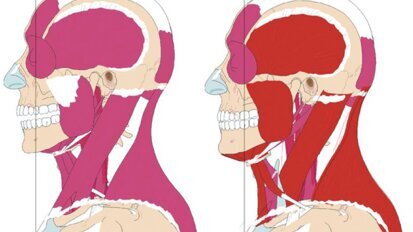

Dentisterie globale prévisible

Dans l'exercice à long terme de la dentisterie globale, la forme, fonction, l'esthétique et la stabilité sont des attributs pour ...